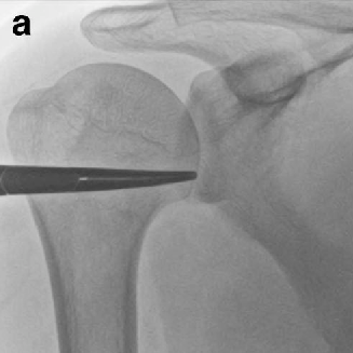

어깨 관절낭 수압 팽창술

염증에 의한 관절낭과 회전근개의 유착을 제거하기 위해 유착을 녹이는 효소제를 주사 할 수 있으며 염증과 부종을 줄여주기 위해 항염증제를 같이 주입합니다. 어깨 관절낭에 최대한 많은 주사액을 주입함으로써 물리적, 화학적으로 유착을 박리하고 조직의 염증과 부종을 줄여줍니다.